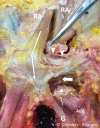

Methods: A layered dissection of the soft tissues of the anterior symphyseal area was performed on seven fresh-frozen male cadavers. The dimensions of the pyramidalis muscle were measured and anatomical connections with adductor longus, rectus abdominis and aponeuroses examined.

Results: The pyramidalis is the only abdominal muscle anterior to the pubic bone and was found bilaterally in all specimens. It arises from the pubic crest and anterior pubic ligament and attaches to the linea alba on the medial border. The proximal adductor longus attaches to the pubic crest and anterior pubic ligament. The anterior pubic ligament is also a fascial anchor point connecting the lower anterior abdominal aponeurosis and fascia lata. The rectus abdominis, however, is not attached to the adductor longus; its lateral tendon attaches to the cranial border of the pubis; and its slender internal tendon attaches inferiorly to the symphysis with fascia lata and gracilis.

Conclusion: The study demonstrates a strong direct connection between the pyramidalis muscle and adductor longus tendon via the anterior pubic ligament, and it introduces the new anatomical concept of the pyramidalis-anterior pubic ligament-adductor longus complex (PLAC). Knowledge of these anatomical relationships should be employed to aid in image interpretation and treatment planning with proximal adductor avulsions. In particular, MRI imaging should be employed for all proximal adductor longus avulsions to assess the integrity of the PLAC.